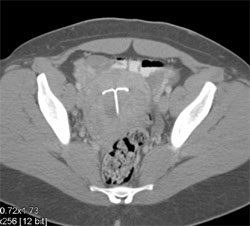

Placenta and Fetus